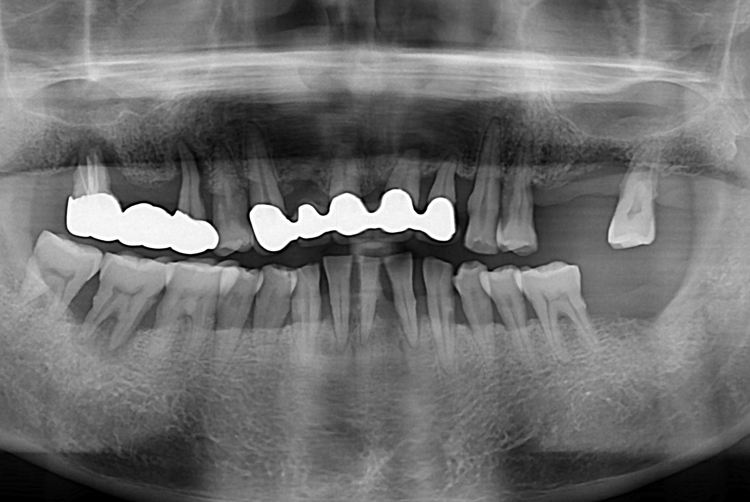

[임플란트] 어금니 임플란트

치료전 : 2019-10-22

치료후 : 2020-01-29

세종치과는 많은 환자와 다양한 케이스를 바탕으로

항상 편안한 임플란트 수술을 제공하고자 노력하고,

오래동안 튼튼히 쓸 수 있는 임플란트 수술을 가장 큰 목표로 삼고 있습니다.